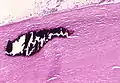

تليف رئوي حاد للغشاء البلوري ونسيج الرئة

"يشير السهم إلى جزء غير مصقول من ألياف الأسبستوس في هذا الجسم الحديدي."